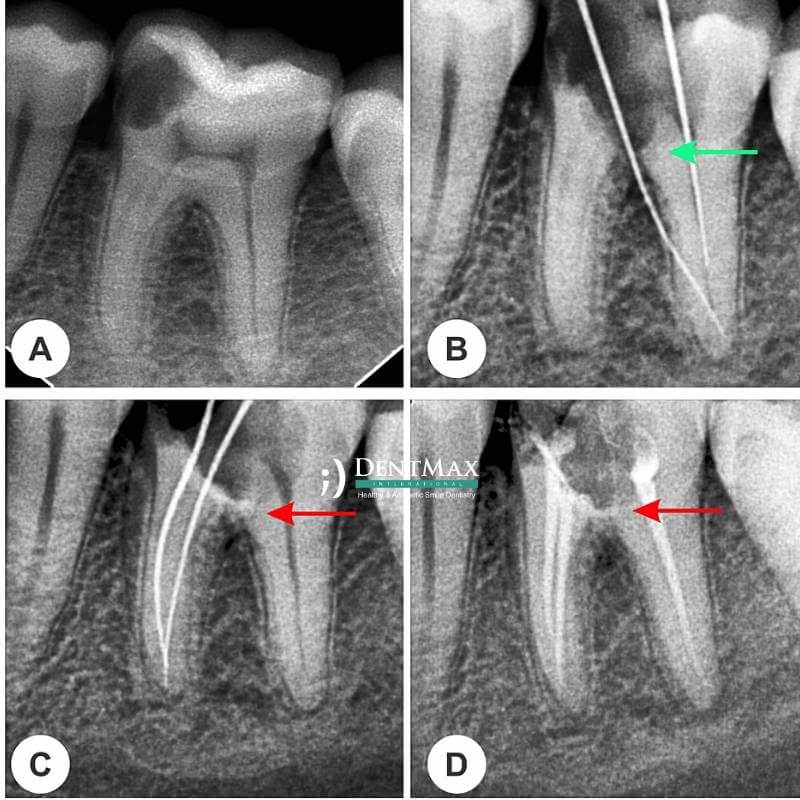

Удаление Сломанного Инструмента